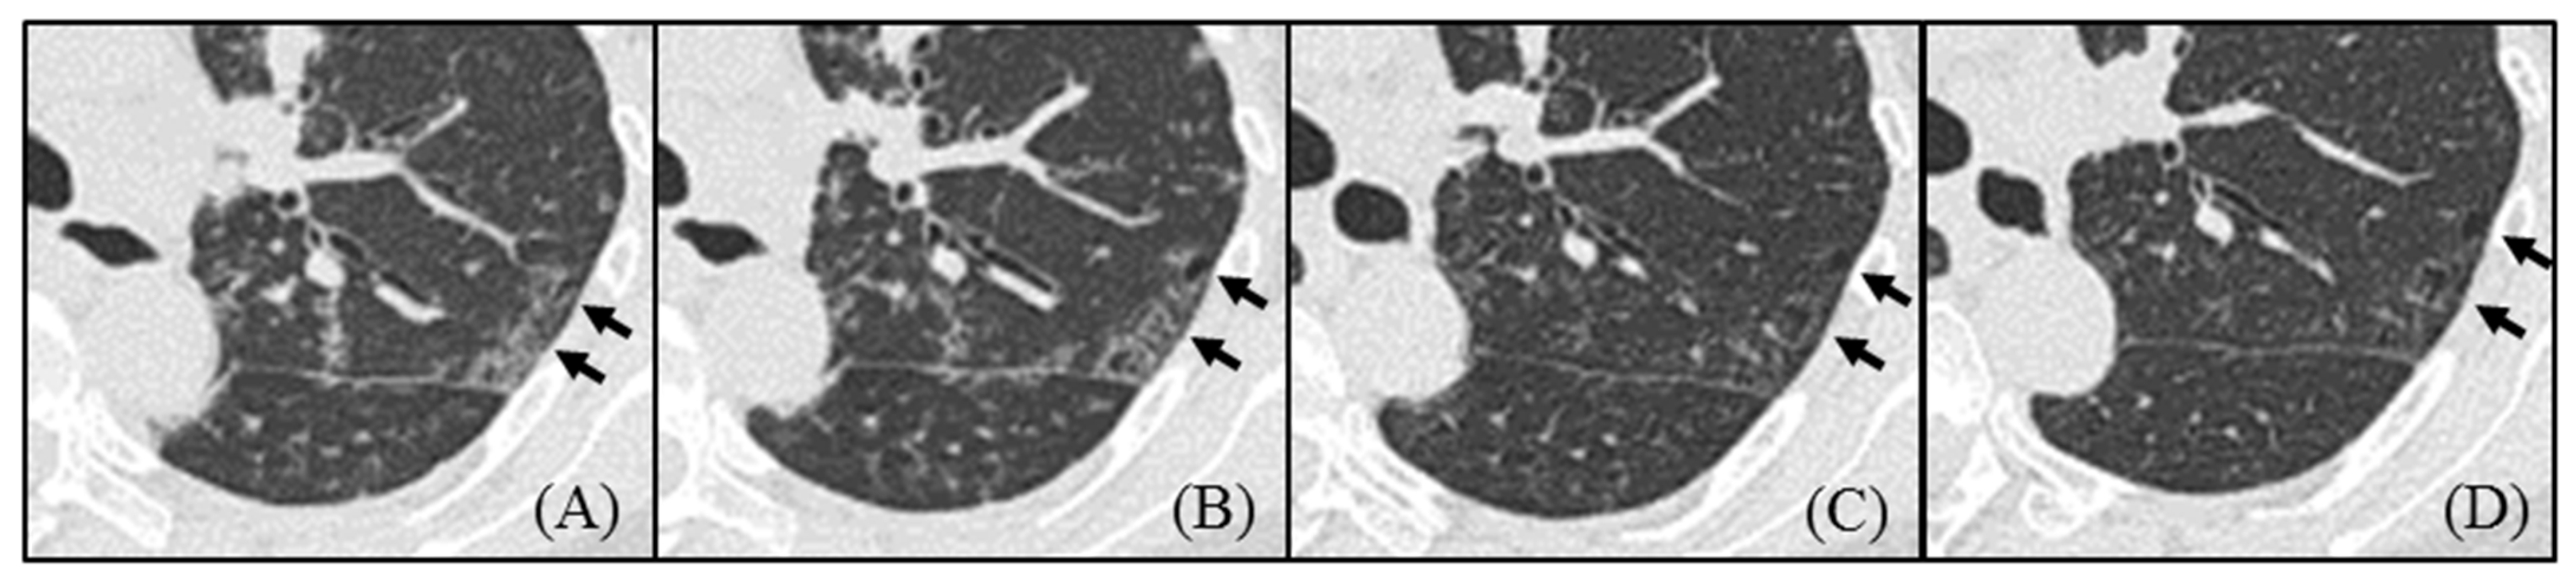

- Pulmonary cysts in idiopathic Castleman disease (MCD) emerged from the area of ground-glass attenuation (GGA) on HRCT, and the cysts did not regress by treatment.

| 8 | + | 32 | 3–9 mm | <2 mm | + | Upper | Interstitial area | TCZ | Increase |